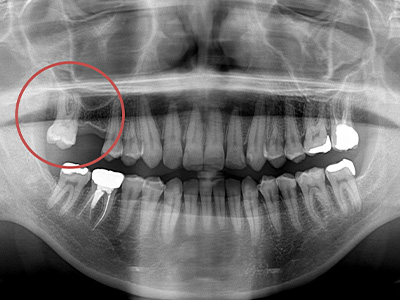

SECOND OPINION

他院でインプラント治療を

断られてしまった方も

決して諦めないでください!

インプラント治療を検討される方の多くは、歯周病が原因で歯を失っており骨を増やす処置が必要になることも少なくありません。近年では、さまざまな骨造成技術の進歩により、これまで困難とされていた症例でも治療が可能になってきました。ただし、これらの処置には高度な技術が求められ、対応できる歯科医師が限られているのが実情です。

当院では、豊富な知識と技術力を活かし、難しいケースにも柔軟かつ的確に対応しておりますので、他院で治療を断られた方も、ぜひ一度ご相談ください。